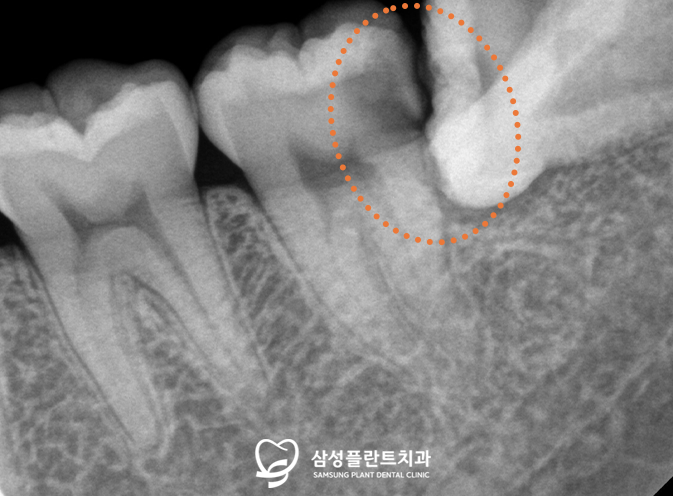

조금 더 정밀한 체크를 위해

치근단 사진을 촬영해 체크해보니,

사랑니로 인한 인접면 충치를

확연하게 체크할 수 있었습니다.

기울어진 사랑니 때문에

충치가 육안으로 잘 관찰되지도 않아,

해당 케이스처럼

충치가 심해진 경우에야

환자분께서 알아차리는 경우가 많답니다..!

해당 치아는 충치가 깊어

신경치료 + 크라운 수복이 필요했습니다.